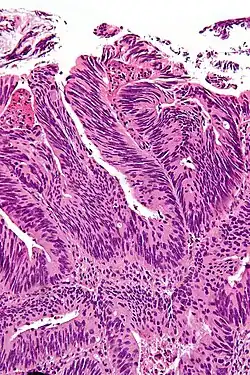

Uzyskanie ujemnego marginesu chirurgicznego jest bardzo ważnym czynnikiem rokowniczym dla wielu nowotworów. Ocena marginesu chirurgicznego jest elementem badania histopatologicznego preparatu po operacji[1].

W zależności od stopnia uzyskanej doszczętności resekcji zmiany margines jest klasyfikowany[2][3]:

- R0 – nowotwór usunięty w zakresie zdrowych tkanek makroskopowo i mikroskopowo (ujemny margines chirurgiczny),

- R1 – nowotwór usunięty makroskopowo w zakresie zdrowych tkanek, ale mikroskopowo stwierdza się naciek nowotworowy w linii cięcia chirurgicznego (dodatni margines chirurgiczny),

- R2 – nowotwór usunięty nieradykalnie mikroskopowo i makroskopowo, naciek nowotworowy jest widoczny bez użycia mikroskopu.